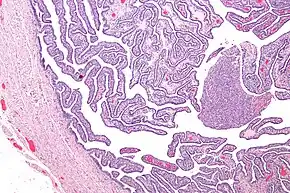

Definitive criteria include histopathologic evidence of endometritis, thickened filled Fallopian tubes, or laparoscopic findings. Gram stain/smear becomes definitive in the identification of rare, atypical and possibly more serious organisms.[22] Two thirds of patients with laparoscopic evidence of previous PID were not aware they had PID, but even asymptomatic PID can cause serious harm.

Laparoscopic identification is helpful in diagnosing tubal disease; a 65 percent to 90 percent positive predictive value exists in patients with presumed PID.[23]